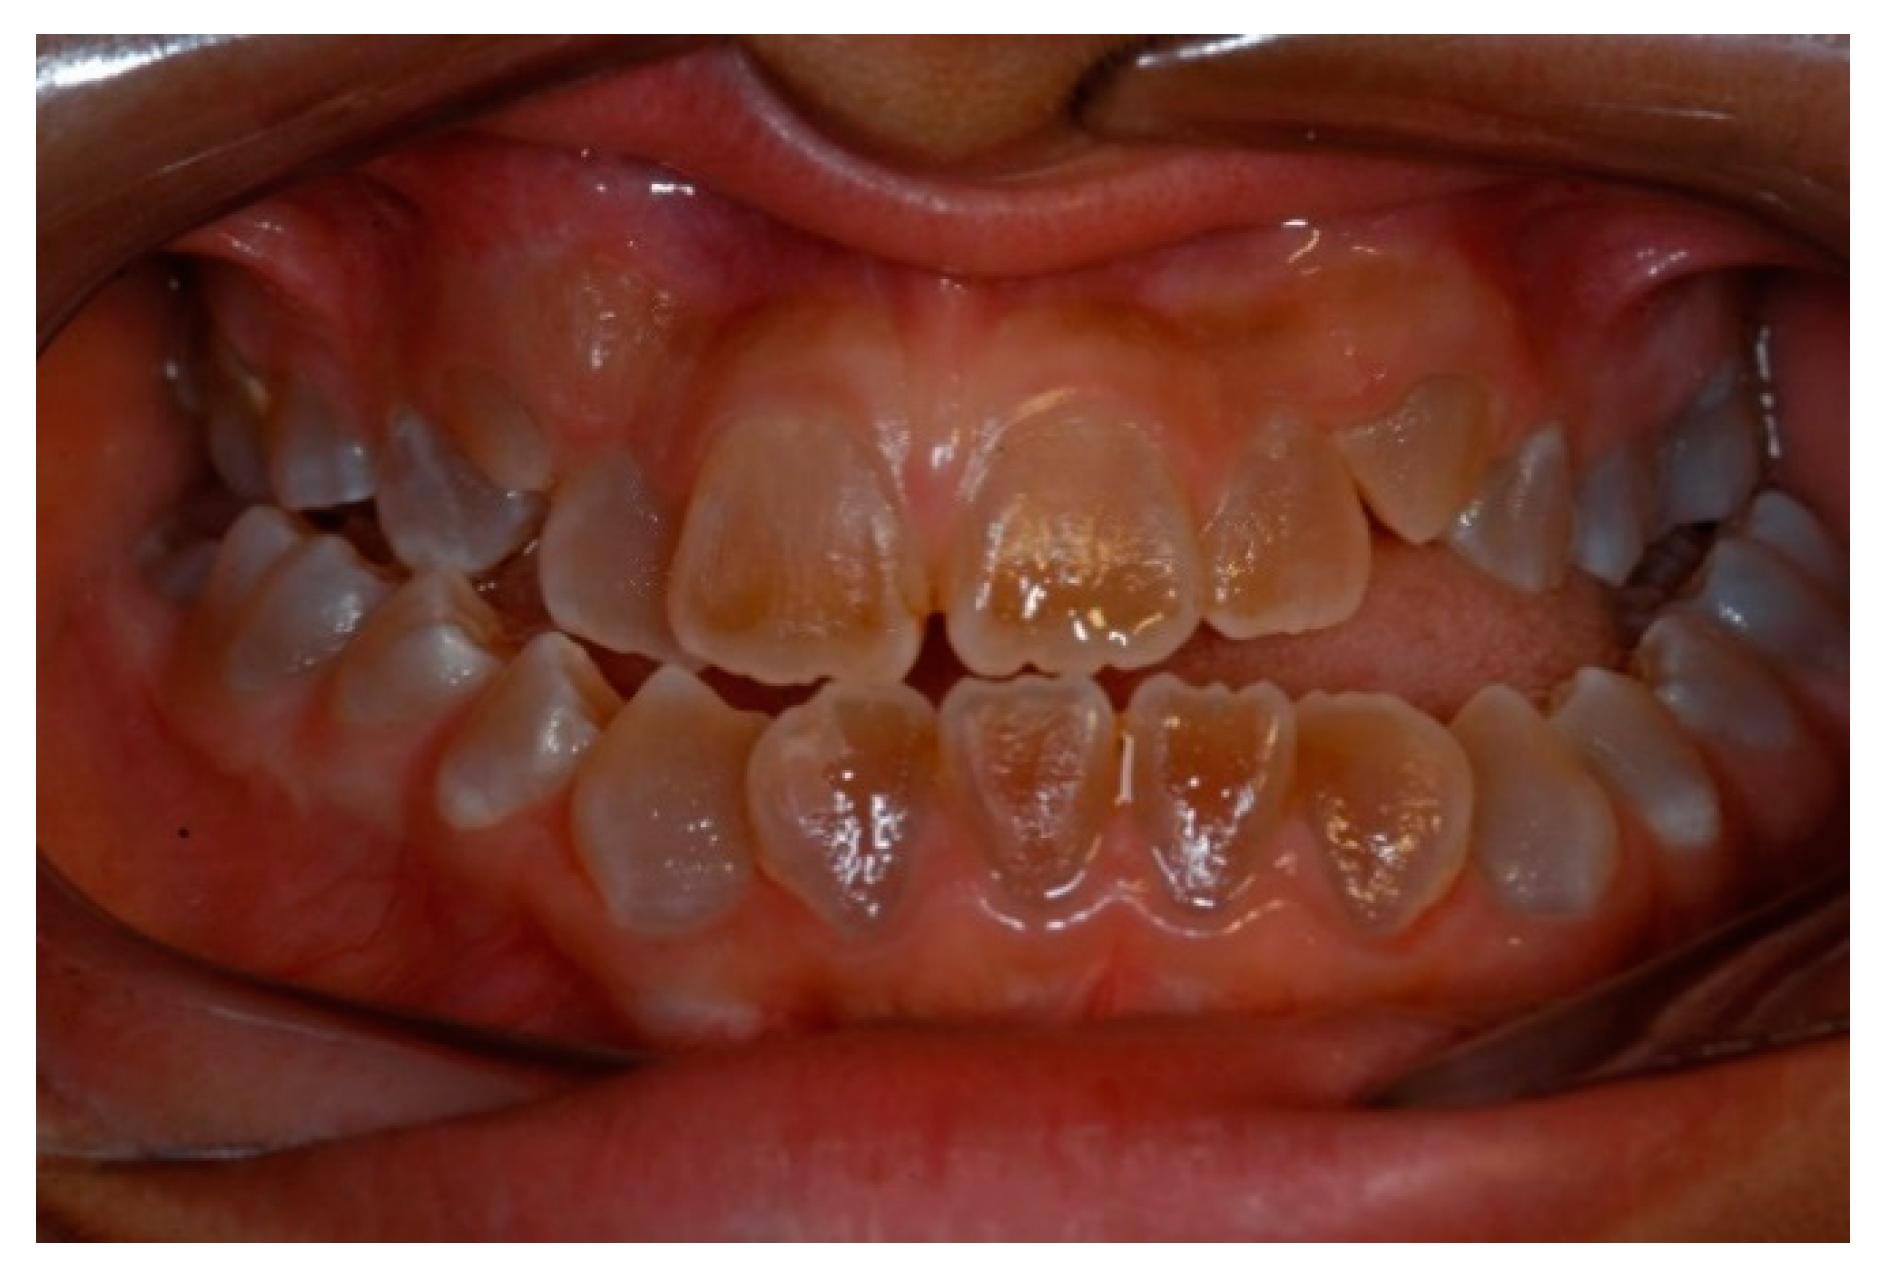

Evaluation of the Severity of Malocclusion in Children with Osteogenesis Imperfecta

3.3. Primary Dentition

4.2. Primary Dentition